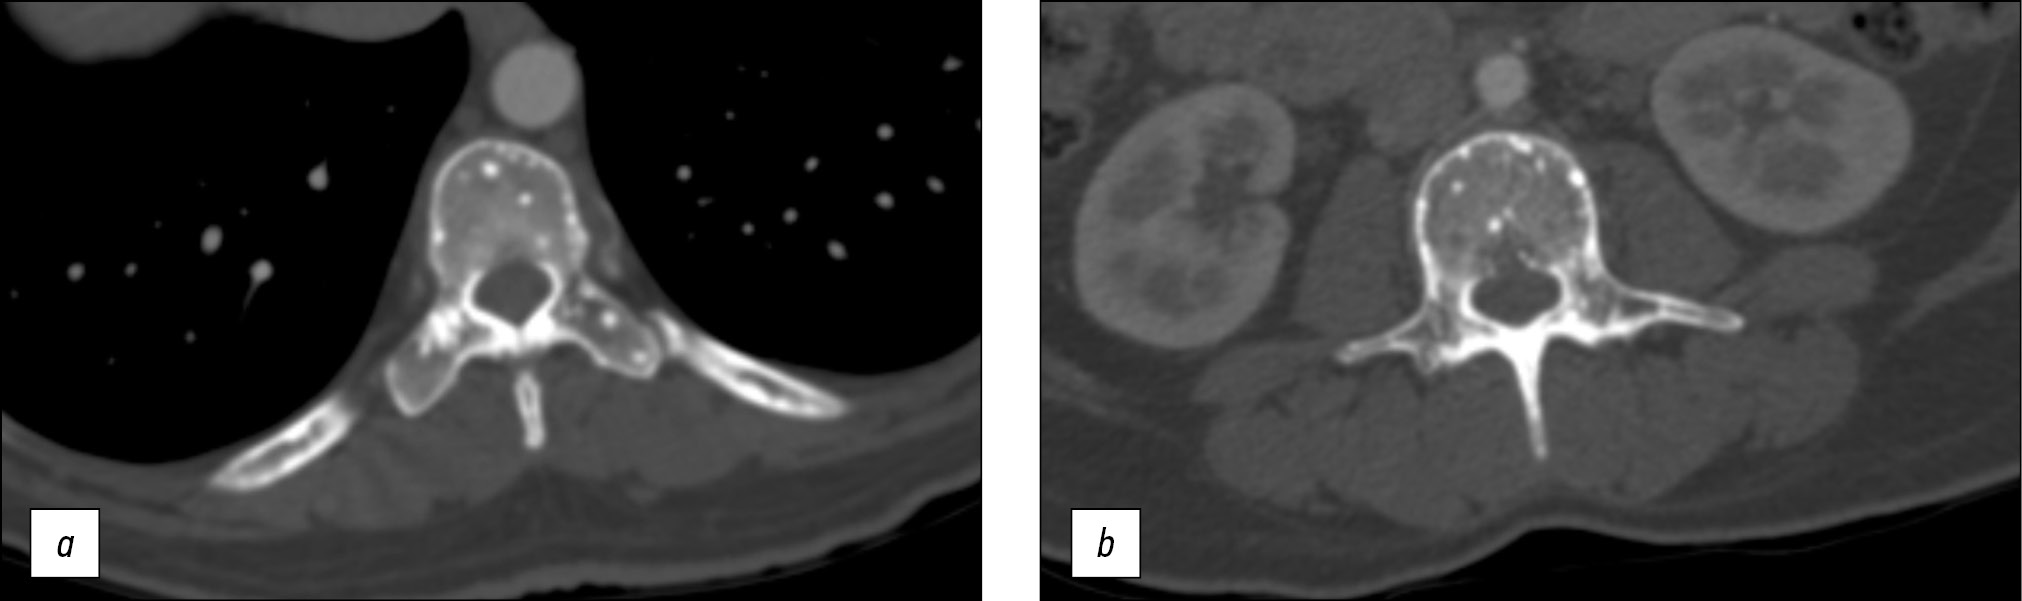

A 43-year-old female patient was taken to the emergency room by ambulance after experiencing transient loss of consciousness. The initial evaluation consisting of history, physical examination, 12-lead electrocardiogram and laboratory tests did not reveal any abnormalities; thus, a total-body computed tomography (CT) was performed. The CT scan showed multiple small sclerotic foci bone islands, scattered throughout the thoracic (Figure 1a) and lumbar spine (Fig. 1b), ribs, pelvic bone (Fig. 2), sacrum (Fig. 3) and bilateral proximal femur (Fig. 4). All bones were free of any cortical erosion or periosteal reaction. No other signs, such as rubor or edema, were noticed; moreover, the patient did not describe any numbness, tingling and weakness in the legs or other parts of the body.

Fig. 1. Transverse cross-section computed tomography scan passing through the thoracic (a) and lumbar (b) spine. It shows numerous, well-defined, homogeneous, circular, hyperdense foci in spinous processes and vertebral arches.